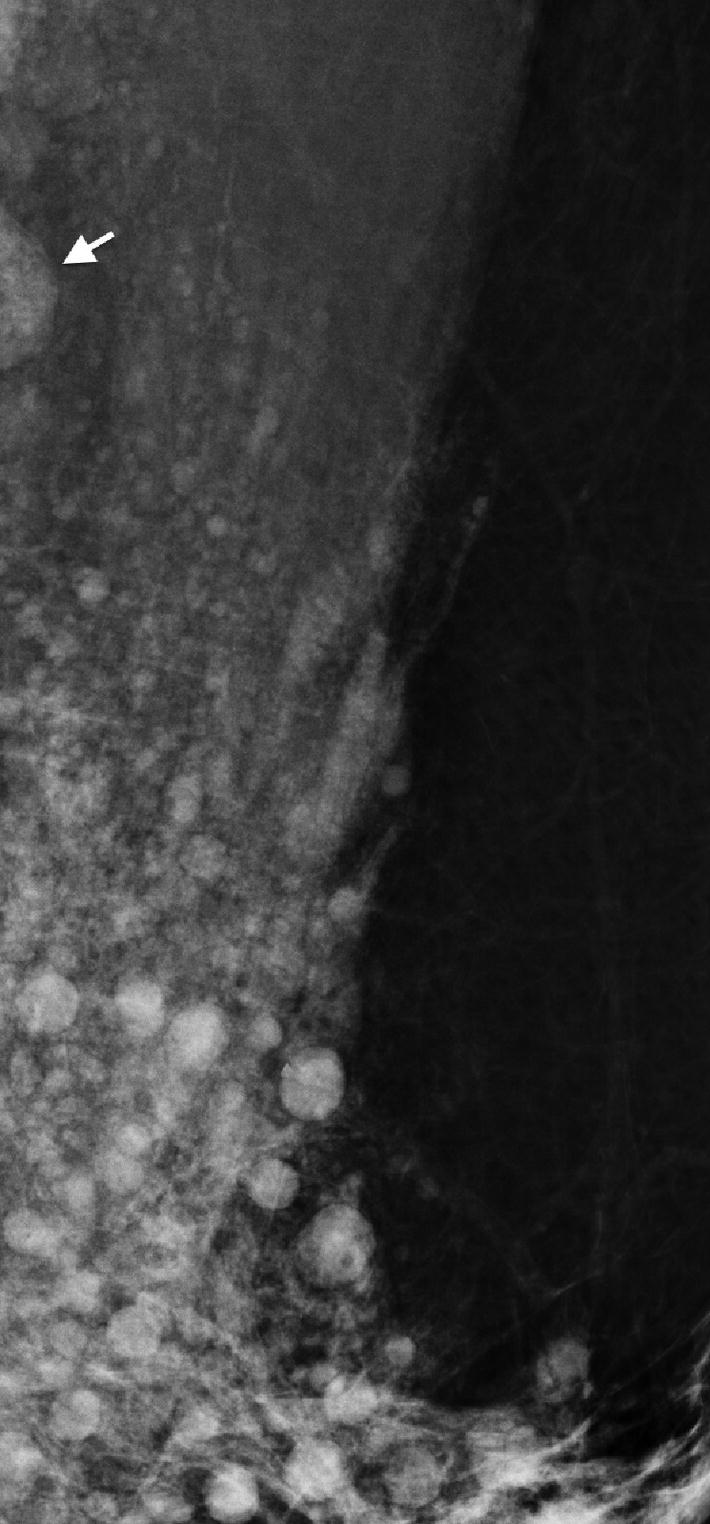

Mammography revealing axillary migration of silicone. Note the numerous siliconomas and infiltration of lymphatic vessels. Note also the partially included high-density lymph node produced by silicone infiltration (arrow)

On some occasions, they are irregular in shape and have poorly defined edges. As a consequence of fibrosis and the ability to migrate, silicone can be identified in all mammary planes, from subdermal to posterior, even capable of infiltrating the pectoral muscle and axilla [1].